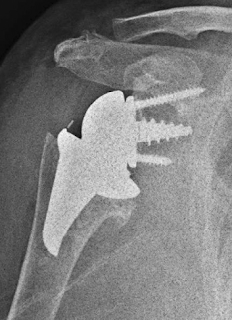

Clinical outcomes were improved. Radiographic analysis showed no lucencies, subsidence, or stress shielding around the humeral or glenoid components. Glenoid notching was found in 21%.

Comment: The authors goal in designing this prosthesis was to preserve humeral bone. It is unclear, however, that their approach is more bone-preserving than an impaction-grafted standard stem as shown below.

We prefer the standard humeral stem with the offset glenosphere shown above because it can manage a wide range of pathologies, some of which (such as that shown below) would be out of reach of a stemless prosthesis.